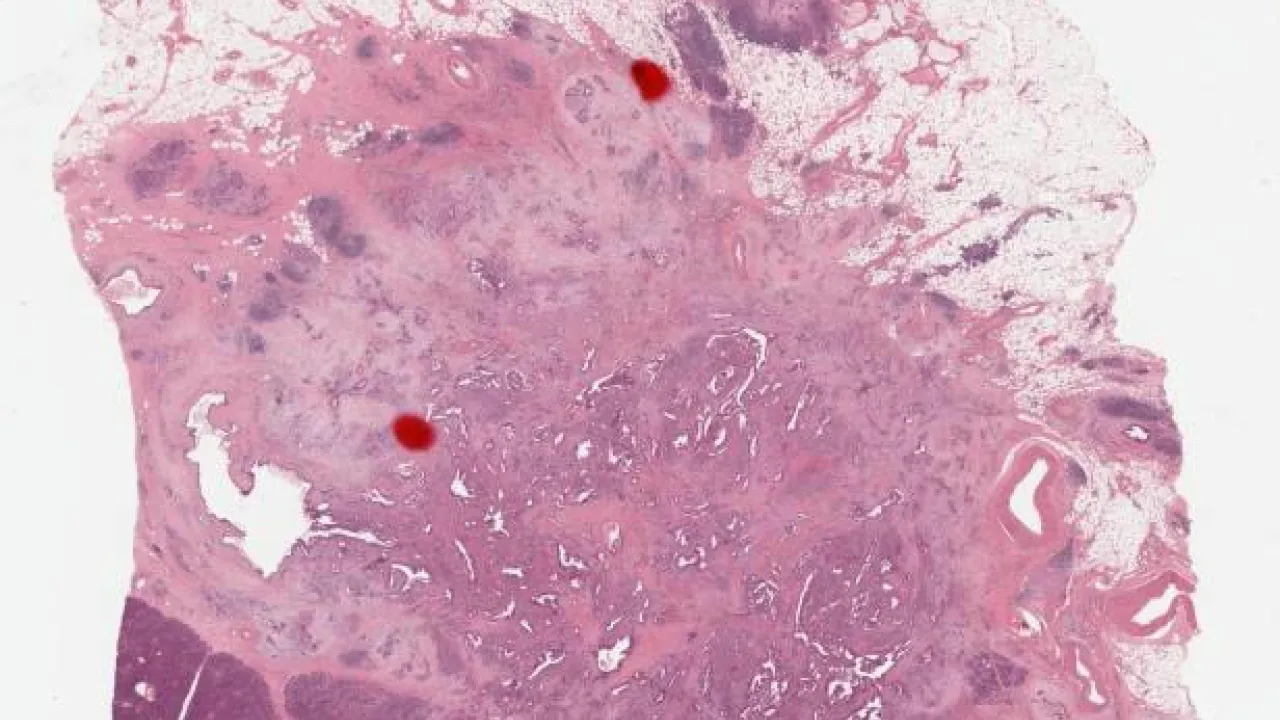

Oral Cavity, Burkitt lymphoma